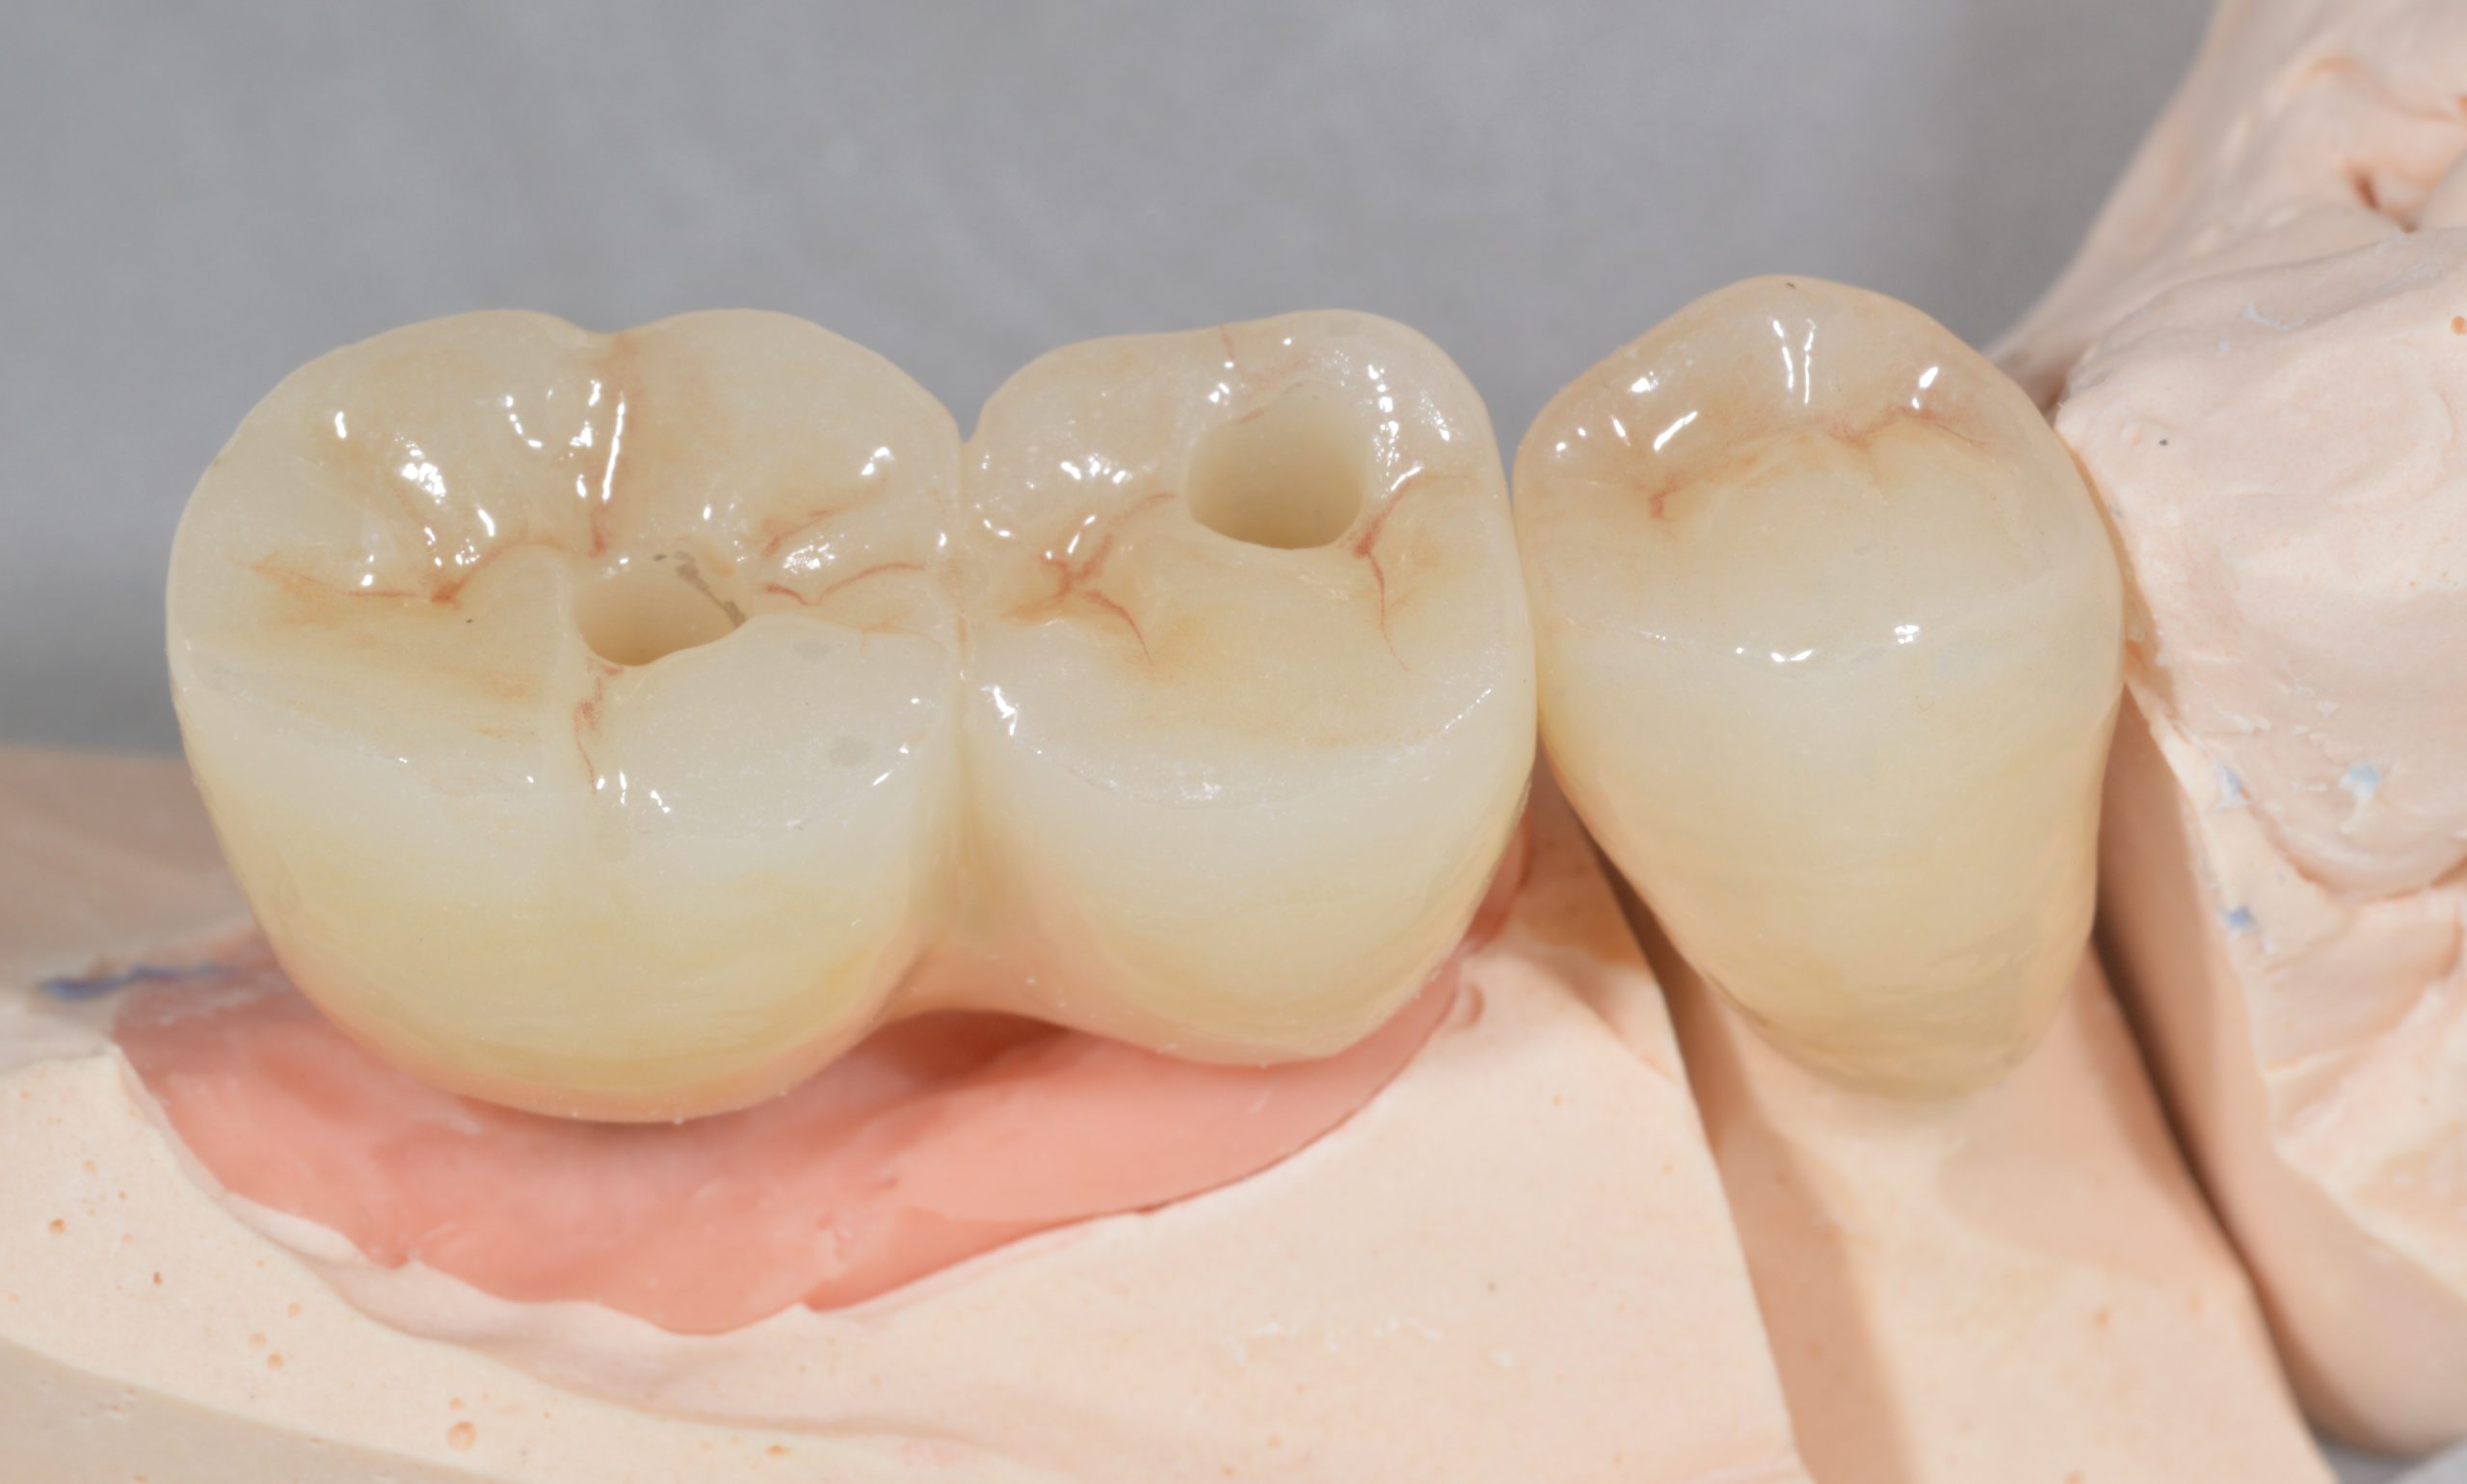

Alle Implantatprothetik sollte nach Möglichkeit durchschraubbar sein, um bei z. B. Bruxismus-bedingten Schraubenlockerungen einen raschen „Servicezugang“ zu haben. Das zahntechnische Meisterlabor strahlte die einprobierten Abutments rau.

Ein ZrO2-Block mit zwei okklusalen Durchgängen wurde angefertigt.